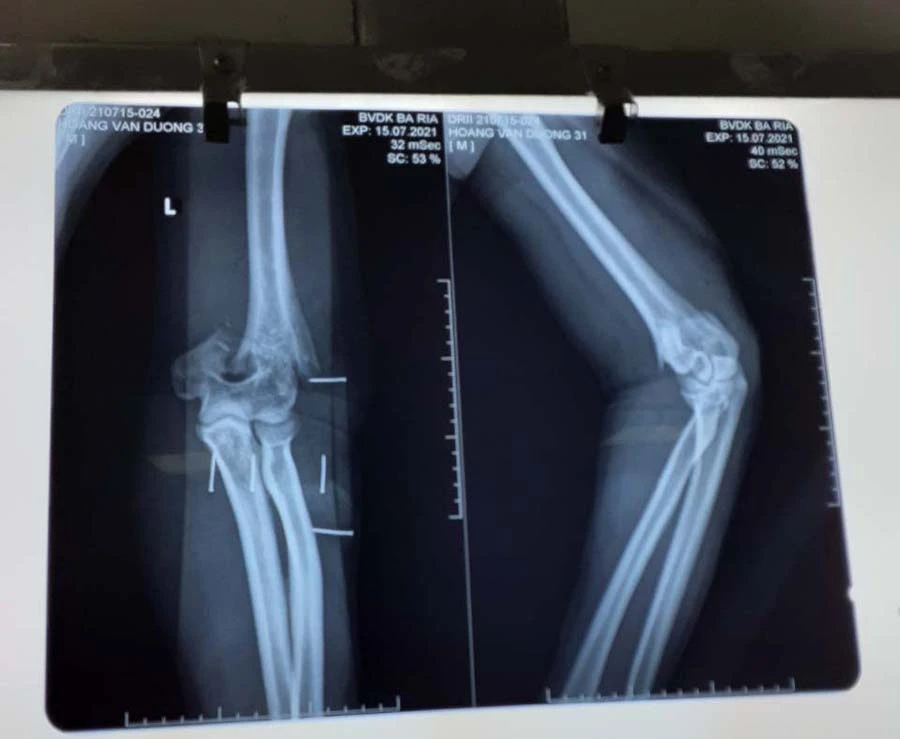

Hình chụp phim thương tích ở cánh tay của thượng úy công an-Ảnh:BV

Trao đổi với PLO, bác sĩ CKI Lại Thế Sở, khoa Ngoại Chấn thương Chỉnh hình, bệnh viện Bà Rịa, tỉnh Bà Rịa- Vũng Tàu- bác sĩ tiến hành phẫu thuật cho thượng úy Dương, cho biết: “Bệnh nhân được chuyển đến cấp cứu tại bệnh viện Bà Rịa chiều 15-7. Sau đó đến 17 giờ chiều cùng ngày được chuyển lên phòng mổ để tiến hành phẫu thuật vết thương khuỷu tay trái. Êkip mổ gồm tôi và bác sĩ Hồ Khắc Tín. Tình trạng vết thương của bệnh nhân trước khi mổ là bị cắt đứt phần gân cơ, phần mềm phía sau khuỷu tay, chém gãy lìa đầu dưới xương cánh tay”.

Các bác sĩ đã phẫu thuật kết hợp xương và khâu nối các cấu trúc bị tổn thương. Sau khi mổ gắn lại xương. Ca mổ tiến hành trong 3 tiếng. Hiện sức khỏe của thượng úy Dương ổn định, chờ thời gian phục hồi các tổn thương.

Theo bác sĩ Sở, bệnh nhân bị một vết chém nhưng gây thương tích nặng, được chuyển viện, cấp cứu kịp thời. Sau này khả năng phục hồi vận động tốt.